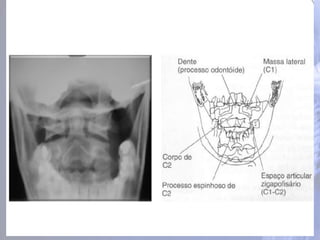

Região cervical (CI– CVII) Os processos espinhosos de C1-6 freqüentemente são bífidos; Todas as vértebras cervicais possuem três forames: um forame vertebral e dois forames transversários

ATLAS (C1) • Nãotem corpo nem processo espinhoso; Face articular superior Processo transvers o Sulco p/ a artéria vertebral e primeiro nervo espinhal Se articula com o osso occipital

ATLAS (CI) faces articularesinferiores se articulam com a segunda vértebra cervical